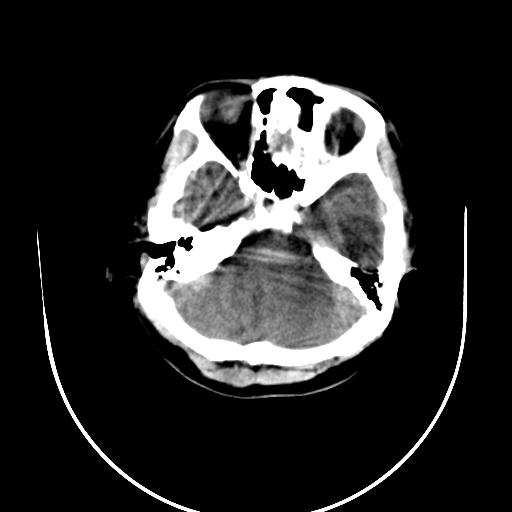

标题: CT10010:女/24岁,癫痫一周,发作时间不固定. [打印本页]

标题: CT10010:女/24岁,癫痫一周,发作时间不固定.

右侧额叶正常吗?

右额叶镰旁饱满.

右侧外侧沟?中央沟?可能有问题,不知以前有没有癫痫过,最好是增强下,排除局部血管畸形等病变

倒数第6幅图中线结构有点偏,而侧脑室额角未见异常,可结合增强扫描。